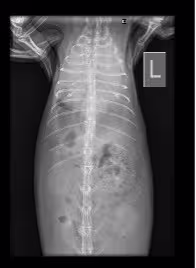

Рентгеновский снимок